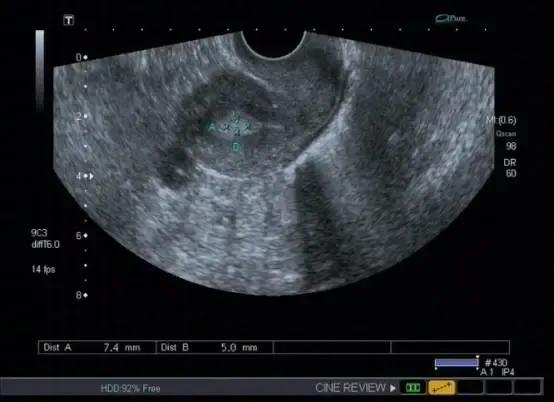

子宫息肉成中-高回声结构,可单个也可多个。

子宫内膜息肉导致宫腔线消失或变形,宫腔内见中-高回声结构,可单发或多个,大小差别很大,常成蛇形,带形或椭圆形。基底部子宫内膜连续可与黏膜下子宫肌瘤鉴别。结节边界清晰,可位于颈管内或宫颈外口。息肉较大时,内膜线显示不清。与子宫内膜癌不易鉴别。 彩色血流显示:中等高阻力的动脉血流或低速的静脉血流信 。 4.子宫内膜息肉病情需要日常监测哪些指标?

标记处息肉